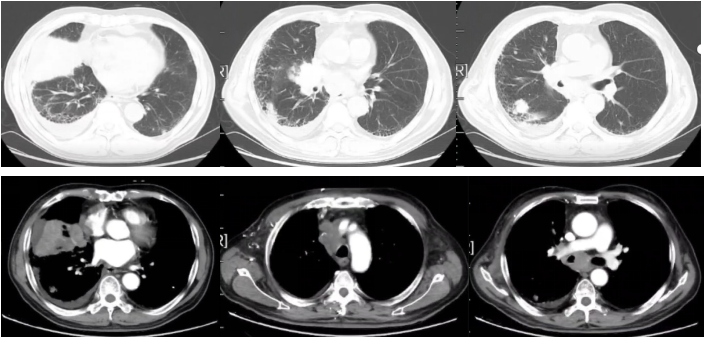

2022-03-31胸部平扫+增强CT:右肺中叶占位(2.6×4.7cm),考虑肺癌,双肺多发小结节(右肺中叶较大者长径约1.8cm),考虑转移。右侧锁区、纵隔及右肺门淋巴结增大(较大者短径约3.2cm),考虑转移。双肺间质性炎。左肺下叶钙化灶。右侧胸腔积液,心包积液。冠状动脉硬化斑块形成。

图1